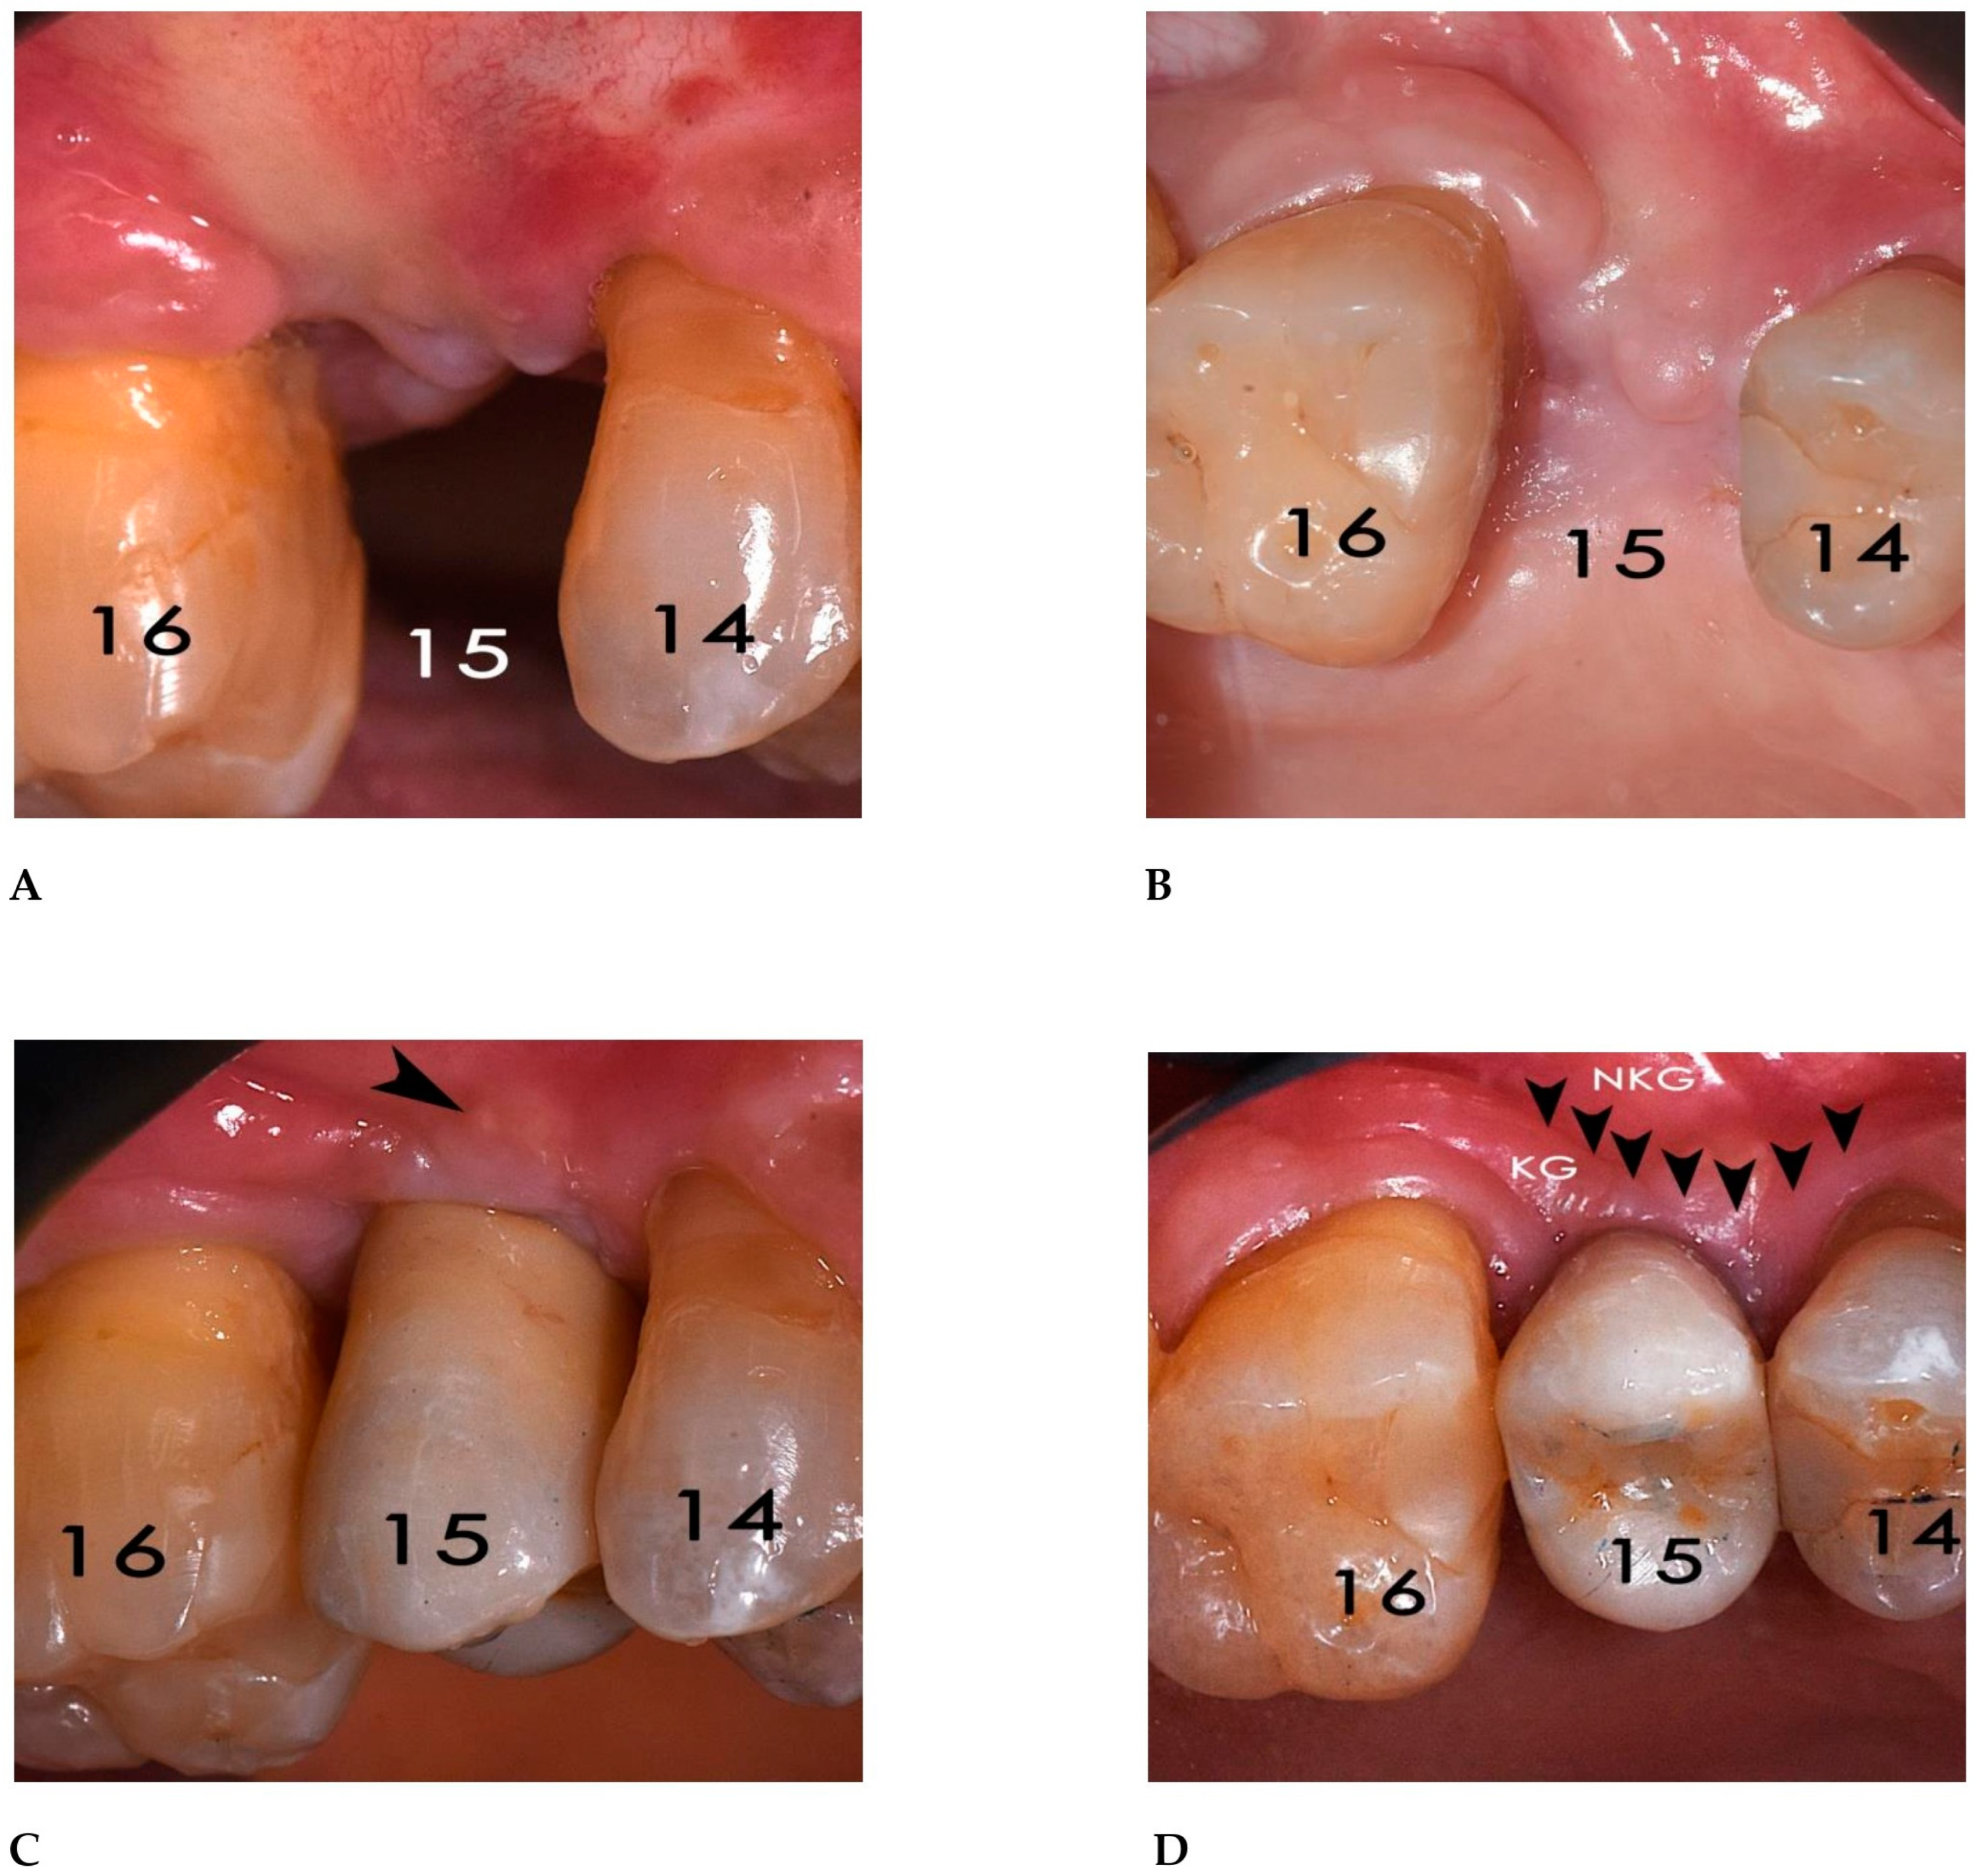

2.3. Surgical and Prosthetic Procedures

3. Results